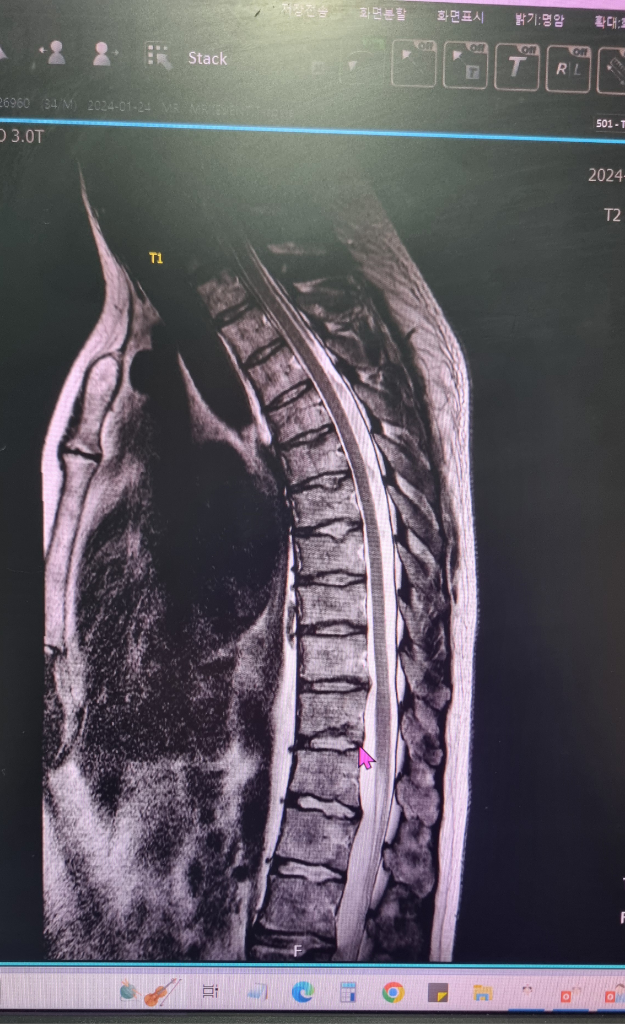

정확한 통증의 원인을 파악하시는게 맞겠습니다. MRI 에는 T1, T2 이런식으로 여러가지 영상이 들어있습니다.

지금 보여주시는 영상은 아마 T2 영상일거라고 생각됩니다. MRI로는 골절이 급성기 상태인지 이전에 있었던 골절인지를 감별할 수 있습니다.

아래 사진중에서 첫번째 사진이 T1 영상이고 두번째 사진이 T2 영상입니다. 보시는것과 같이 급성기 골절에서는 T1에서 검정색으로 보이고 T2에서는 하얀색으로 보이는 특징을 가지고 있습니다. 그런데 올려주신 사진 T2 에는 음영이 증가해있지 않습니다. 즉, 최근에 부러진게 아니고 이전에 부러졌는데 지나갔던 병변일 가능성이 높다는 의미입니다. 이런 경우는 주로 디스크 손상과 연관된 종판손상으로 생각할 수 있습니다.